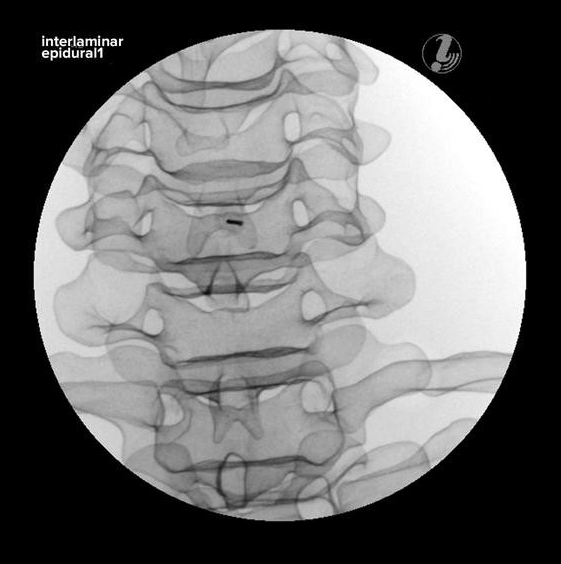

TRENAŻER ZNIECZULANIA ZEWNĄTRZOPONOWEGO W ODCINKU SZYJNYM POD KONTROLĄ USG

Trenażer znieczulania zewnątrzoponowego w odcinku szyjnym pod kontrolą USG umożliwia naukę diagnozowania źródła bólu, identyfikacji tkanki docelowej i narażonych struktur, przy użyciu USG i anatomicznych punktów. Prezentowany model to alternatywa dla pracy ze zwłokami. Model jest wytrzymały i zawsze dostępny do przeprowadzania ćwiczeń.

• realistyczne obrazy X-ray

• realistyczna symulacja znieczulenia

CECHY: Trenażer znieczulania zewnątrzoponowego w odcinku szyjnym pod kontrolą USG